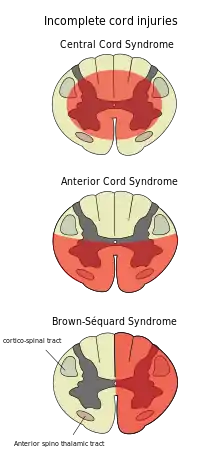

Синдром центромедулярного ураження

Синдром центромедулярного ураження майже завжди є наслідком пошкодження шийного відділу спинного мозку й характеризується слабкістю в руках з відносною збереженістю ніг і пошкодженням чутливості в ділянках, що інервуються крижовими сегментами. [23] Втрачається відчуття болю, температури, легкого дотику та тиску нижче рівня травми. [24] Спинальні провідні шляхи, які обслуговують руки, більше уражені через центральне розташування їх у спинному мозку, в той час як кортикоспінальні волокна (шляхи від кори lat. cortex), призначені для ніг, збережені через своє зовнішнє розташування. [24] Найбільш поширений із неповних синдромів спинальної травми, синдром центромедулярного ураження, як правило, є наслідком гіперекстензії шиї (через запрокидування голови) у людей похилого віку зі стенозом хребта. У молодших людей він навпаки, частіш є результатом згинання шиї. [25] Найпоширеніші причини — падіння та ДТП; однак інші можливі причини включають спинальний стеноз та пошкодження спинного мозку пухлиною чи килою міжхребцевого диску. [26]

Синдром переднього рогу

Внаслідок пошкодження мозку або зменшення кровопостачання передньою спинномозковою артерією може виникати синдром передньго рогу. Він зазвичай викликаний переломами, вивихами хребців або килою диску. [24] Нижче рівня травми втрачаються, рухові функції, больові та температурні відчуття, а відчуття дотику та пропріоцепції (почуття положення в просторі) залишаються неушкодженими. [27] [25] Ці відмінності пояснюються відносним розташуванням спинальних трактів, що відповідають кожен за свій тип функції. [24]

Синдром Брауна-Секара

Синдром Браун-Секара (Brown-Séquard syndrome рос — см Броун-Секара) виникає, коли спинний мозок з одного боку травмований набагато більше, ніж з іншого. [28] Насправді рідко коли спинний мозок може бути дійсно чітко наполовину пошкоджений (перетнутий з однієї сторони), натомість часткові ураження через проникаючі рани (наприклад, вогнепальні чи ножові), або переломи хребців та пухлини досить поширені. [29] На іпсилатеральній (на тій самій) стороні від травми організм втрачає рухову функцію, пропріоцепцію, вібраційні та тактильні відчуття вібрації й дотику. [28] На контралатеральній (протилежній від травми стороні) спостерігається втрата болю та температурних відчуттів. [26] [28]